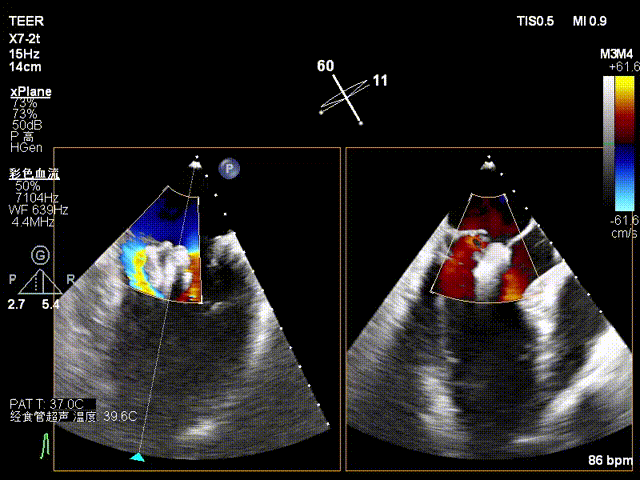

患者为73岁老年男性,经食道超声检查提示:急性二尖瓣腱索断裂合并反流,前叶长度:2.8cm,后叶长度:1.7cm,脱垂宽度:18mm,脱垂高度:8mm,瓣口面积:6.5cm²。

X-plane2区

X-plane2区彩色

X-plane 1区

X-plane 2区

X-plane 2区彩色